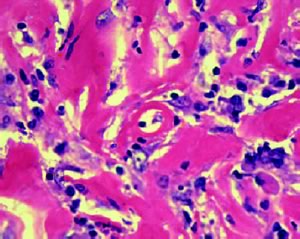

Negli stadi precoci di formazione della massa fibrosa, istologicamente si dimostra la presenza di una importante componente cellulare costituita in particolare da linfociti, eosinofili, leucociti polimorfonucleati ed altre cellule dell'infiammazione immerse in una matrice di collagene; progressivamente, per�, tale tessuto fibrotico tende a divenire sempre pi� acellulare.

Figura 2. Preparato istologico di fibrosi retroperitoneale; importante infiltrato infiammatorio immerso tra bande di tessuto collagene. (S. Jogai, A. Al-Jassar and L. Temmim. Cytopathology 2005, 16, 49�54)